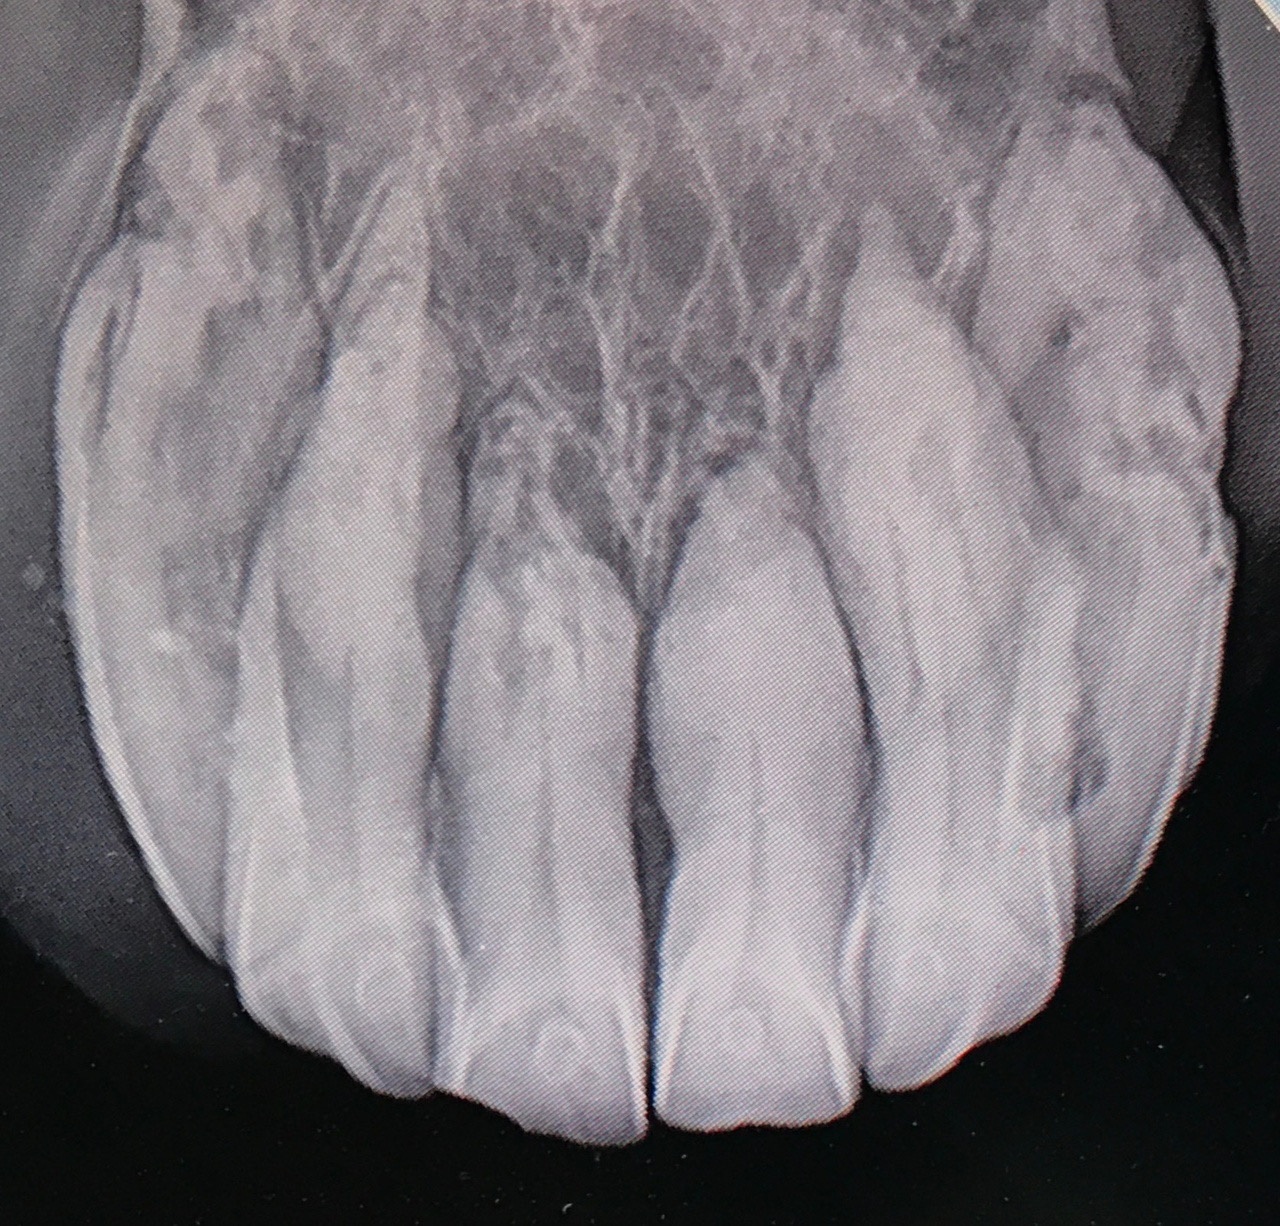

Mastering EOTRH

Join us for our popular Masterclass series where we discuss how to recognise, assess, grade, treat, refer and talk to owners about odontoclastic tooth resorption and hypercementosis

Learn how to radiographically grade EOTRH resorptive lesions and properly assess affected horses.